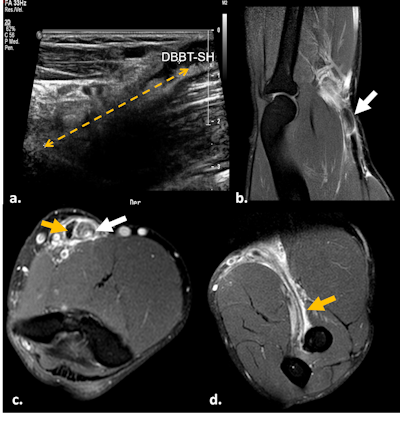

BAMIC 3b injury. Fat-suppressed proton-density weighted axial (a) and coronal images (b) show muscle edema >15 cm (white dotted line) at the myotendinous/intramuscular tendon, with tendon distortion >5 cm (orange dotted line) with a wavy appearance. Interfascial hematoma and surrounding the ischiatic nerve (black arrow). Semitendinous (ST), biceps femoris (BF).